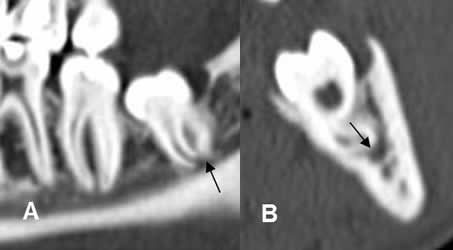

Fig 18 A. Canal mandibular.

A : TAC reconstrucción sagital y B: TAC reconstrucción transversal. Raíz de la pieza 48, que deforma el contorno de la parte supero-interna del canal mandibular.

Fig 18 B. Deformidad canal dental.

A: TAC reconstrucción sagital y B: TAC reconstrucción coronal. Canal dentario en contacto con la cortical del hueso y comprimido medialmente por la raíces de la pieza 38.